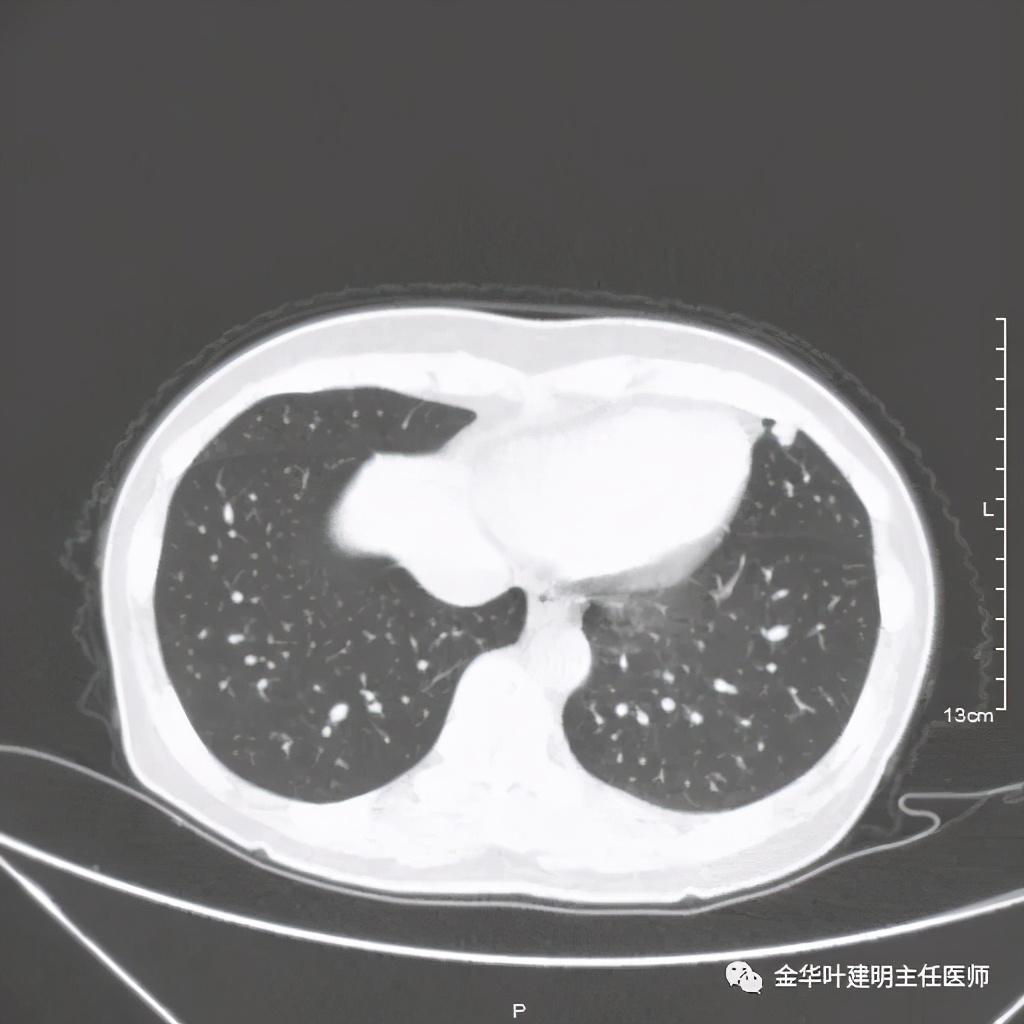

五、浸润性腺癌之粘液腺癌:

影像特征:这个病例是我在术前仅凭影像就判断其为粘液腺癌,术后确诊的。粘液腺癌表现为 实性乏收缩力、密度较均匀 的实性结节。病灶的边界一般非常清楚,没有毛刺、磨玻璃、卫星灶等,但又乏收缩力,像本例紧贴胸膜也不会有牵拉凹陷;同时病灶的密度又比较均匀(粘液成份)。良性肿瘤密度要更高些、慢性炎没有这么光整的边界,也容易有瘢痕收缩方面的影像表现、其他实性的腺癌则要有收缩力、腺泡型虽然也缺乏收缩力,但密度要不均匀些。